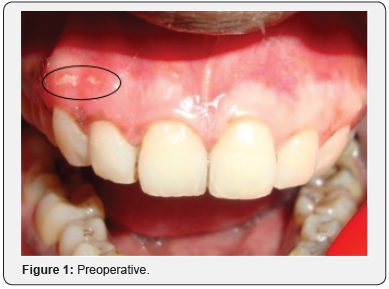

A 25-year-old male patient reported with the complaint of dark colored gums. Gingival depigmentation was performed with diode laser in both maxillary and mandibular arches in the intercanine region. Three months postoperatively, the patient reported with pain in the attached gingiva of the maxillary right lateral incisor and canine. On examination, a bony sequestrum surrounded by erythema was observed in the gingiva overlying the maxillary right lateral incisor and canine (Figure 1). A sub marginal incision was given with a 15 no.B.P.blade in the attached gingiva extending from the maxillary right lateral incisor to the maxillary right first premolar. A full thickness flap was reflected to perform alveoloplasty for removal of the bony sequestrum and reshaping of the underlying bone. On removal of the sequestrum, an alveolar dehiscence was found in relation to the maxillary right canine, measuring up to 6 mm from the gingival margin (Figure 2). Alveoloplasty was performed; the flap was repositioned and sutured with 5-0 black silk and postoperative instructions given (Figure 3). Antibiotic and analgesic were prescribed for 5 days. Erythema was absent one week postoperatively, but slight pain was reported (Figure 4). On one month follow up, the gingiva was pink, firm and resilient with stippled appearance and absence of pain (Figure 5).